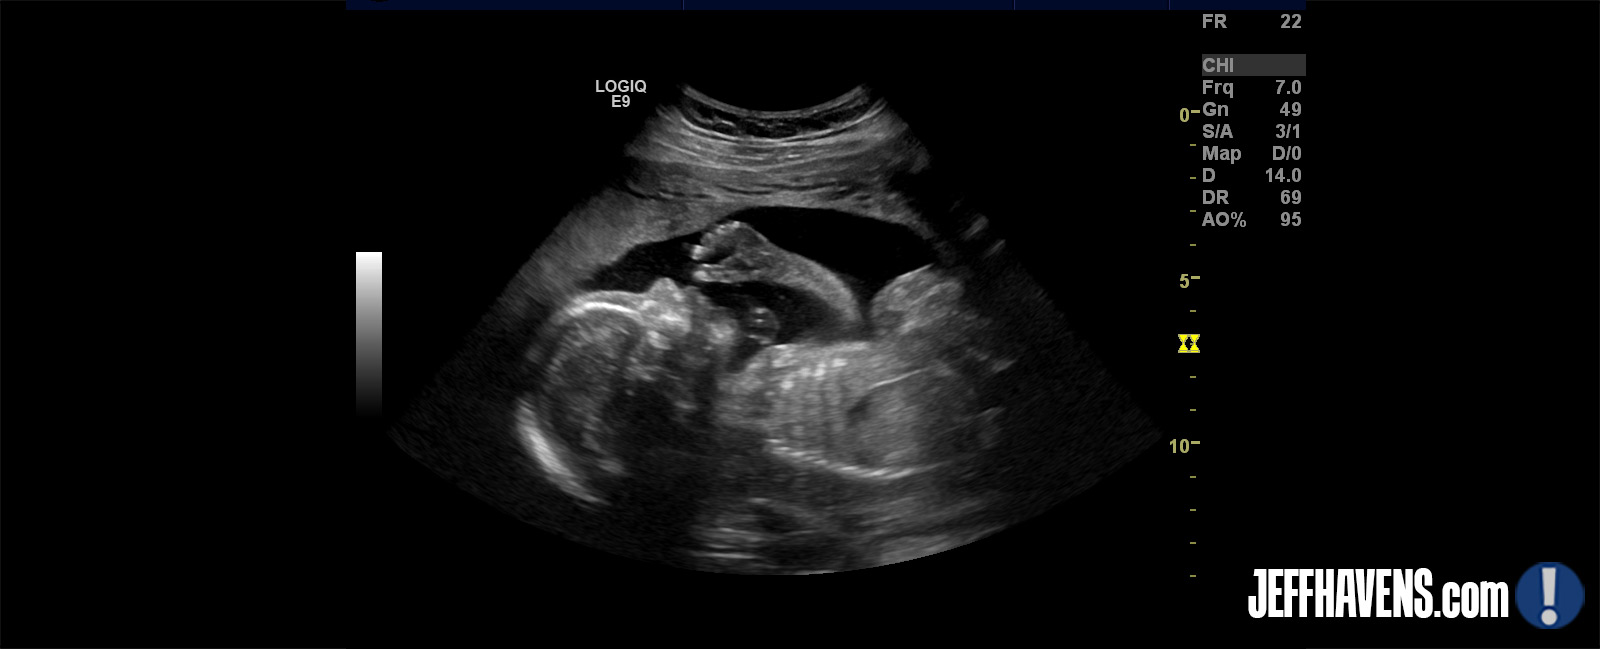

When we went for our 8-week ultrasound, we were told that babies grow at virtually uniform rates until about the 10th or 11th week, which means that it’s fairly easy to predict due dates based on the size. In our case, the ‘crown to rump’ length was 1 centimeter, and we were told that we were officially 7 weeks and 1 day pregnant, and that our due date was therefore February 16. Which all sounded very scientifically and official – until they changed the due date on us at the 20-week ultrasound. And such is life. Doctors assure us that they know what’s going on while simultaneously telling us to get a second opinion, and we confidently predict what will happen in the next three months at work only to sometimes get thrown a wicked curveball. I think most of our stress comes from trying to control things we can’t control – which is almost everything. I hope I’m able to recognize what I can and can’t control once our child is born, as I believe it will be the key to my future sanity. (The new due date is February 9, by the way. Or maybe January. Or 2024. Who knows?)